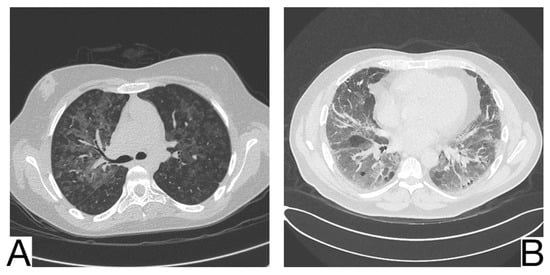

10.7. Hypersensitivity Pneumonia

It is an interstitial pathology caused by the inhalation and repeated sensitization of a wide range of inorganic and organic antigens, occupationally or from the environment. Radiological characteristics for differential diagnosis (Figure 9A): centroparenchymal and centrolobular ground glass opacities; the rare appearance of cobblestone and pulmonary condensations; coexistence of other radiological aspects such as oligemia, cysts, centrolobular emphysema, and centrolobular micronodules; coexistence of ground glass opacities, preserved lung regions and air trapping on HRCT (Figure 9B); centrolobular fibrosis, architectural distortions, traction, and bronchiectasis in the chronic phase; mediastinal lymphadenopathy.

Figure 9. Hypersensitivity pneumonia (A). Perihilar ground glass changes (B). Gas trapping on the expiratory image, ground glass opacity, and honeycombing. Note. Case courtesy of Dr. Yi-Jin Kuok, Radiopaedia.org, rID: 17192 (A) and Dr. Henry Knipe, Radiopaedia.org, rID: 48107 (B).